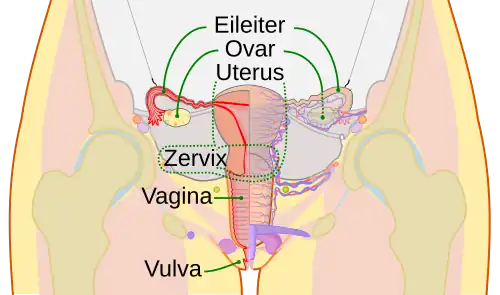

Die Vagina des Menschen, deutsch Scheide (des Menschen) genannt, ist ein mit Schleimhäuten ausgekleidetes, primäres, inneres Geschlechtsorgan der Frau. Sie verbindet, wie die Vagina anderer Säugetiere, die Gebärmutter (den Uterus) über den Gebärmutterhals (die Zervix) mit dem Scheidenvorhof (Vestibulum vaginae). Am Übergang zu letzterem befindet sich der Hymen (Jungfernhäutchen). Die Vagina ist Teil des Geburtskanals.

Die Vagina ist ein dehnbares, muskulös-bindegewebiges, mit einer Schleimhaut ausgekleidetes Organ im Bauchraum. Sie liegt etwa in der Beckenachse[1] und durchquert hier den Beckenboden.[2] Die Vagina verbindet den Scheidenvorhof mit der Gebärmutter (Uterus). Der Gebärmutterhals ist um etwa 90 Grad nach vorn abgeknickt und folgt damit nicht der durch die Vagina vorgegebenen Richtung.

Uterusseitig ragt die Portio vaginalis uteri des Gebärmutterhalses in die Vagina vor. Diese wird von der Vagina so umfasst, dass sie zwischen dem tiefen, hinteren (dorsalen), sowie dem kleineren seitlichen und dem vorderen (ventralen) flachen Scheidengewölbe (Fornix vaginae) liegt.[2] Das hintere Scheidengewölbe reicht bis an den Douglas-Raum heran,[2] einer taschenförmige Aussackung des Bauchfells und damit der tiefste Teil des Bauchraums zwischen Mastdarm und Uterus.